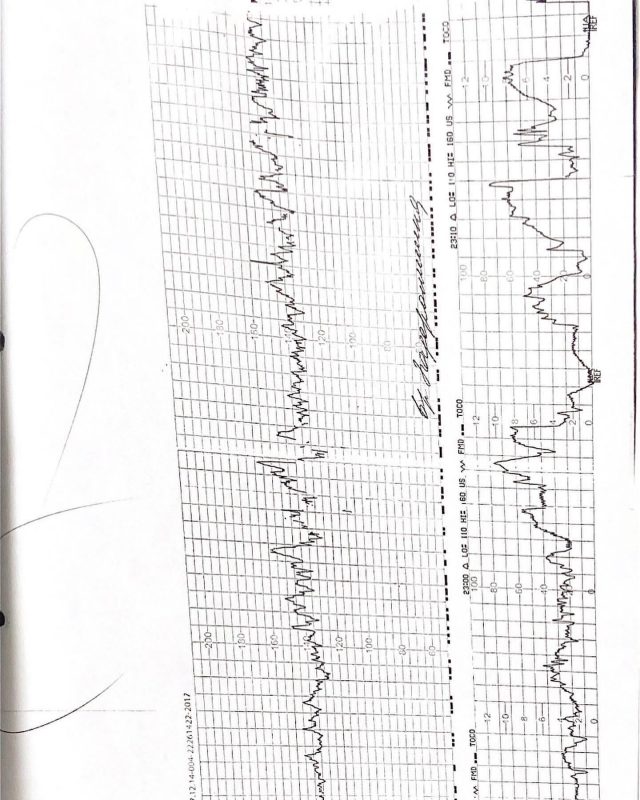

По её словам, медики не проверяли КТГ (кардиотокография — непрерывная синхронная регистрация частоты сердечных сокращений плода и тонуса матки с графическим изображением сигналов на калибровочной ленте), и только в час ночи, спустя 18 часов, решили предпринять меры по родовспоможению.

«Моего здорового ребёнка просто убили. 19 часов безводного периода дало о себе знать! Ребёнок просто задохнулся, и в этом, я считаю, виноваты врачи, на все мои просьбы о кесарево и о том, что я не могу сама родить, о том, что у меня нет сил, просто отшучивались, отмахивались! И да, на КТГ, которое велось у меня с самого поступления в роддом, почему-то отсутствует именно время с 22:10 до 1:10! Хотя в это время КТГ велось! Могу предположить, что скрыли именно эту часть, для своей выгоды!